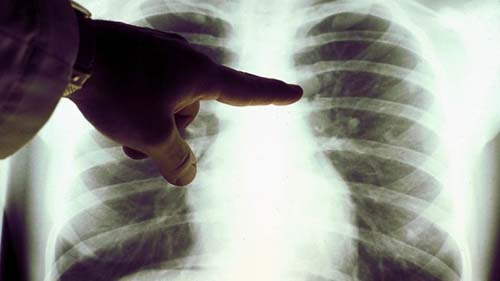

Ele foi diagnosticado com linfoma de Hodgkin clássico em estágio III (o linfoma afeta áreas de glânglios localizadas em ambos os lados do diafragma ou por cima do diafragma e no baço).

Logo após o diagnóstico, ele foi internado com falta de ar e diagnosticado com pneumonia por SARS-CoV-2, confirmado com exame PCR positivo. Após 11 dias, ele foi liberado para convalescer em casa. Corticosteroides e imunoquimioterapia não foram administrados.

Quatro meses depois, o inchaço dos nódulos havia diminuído e um PET scan revelou uma remissão generalizada do linfoma.